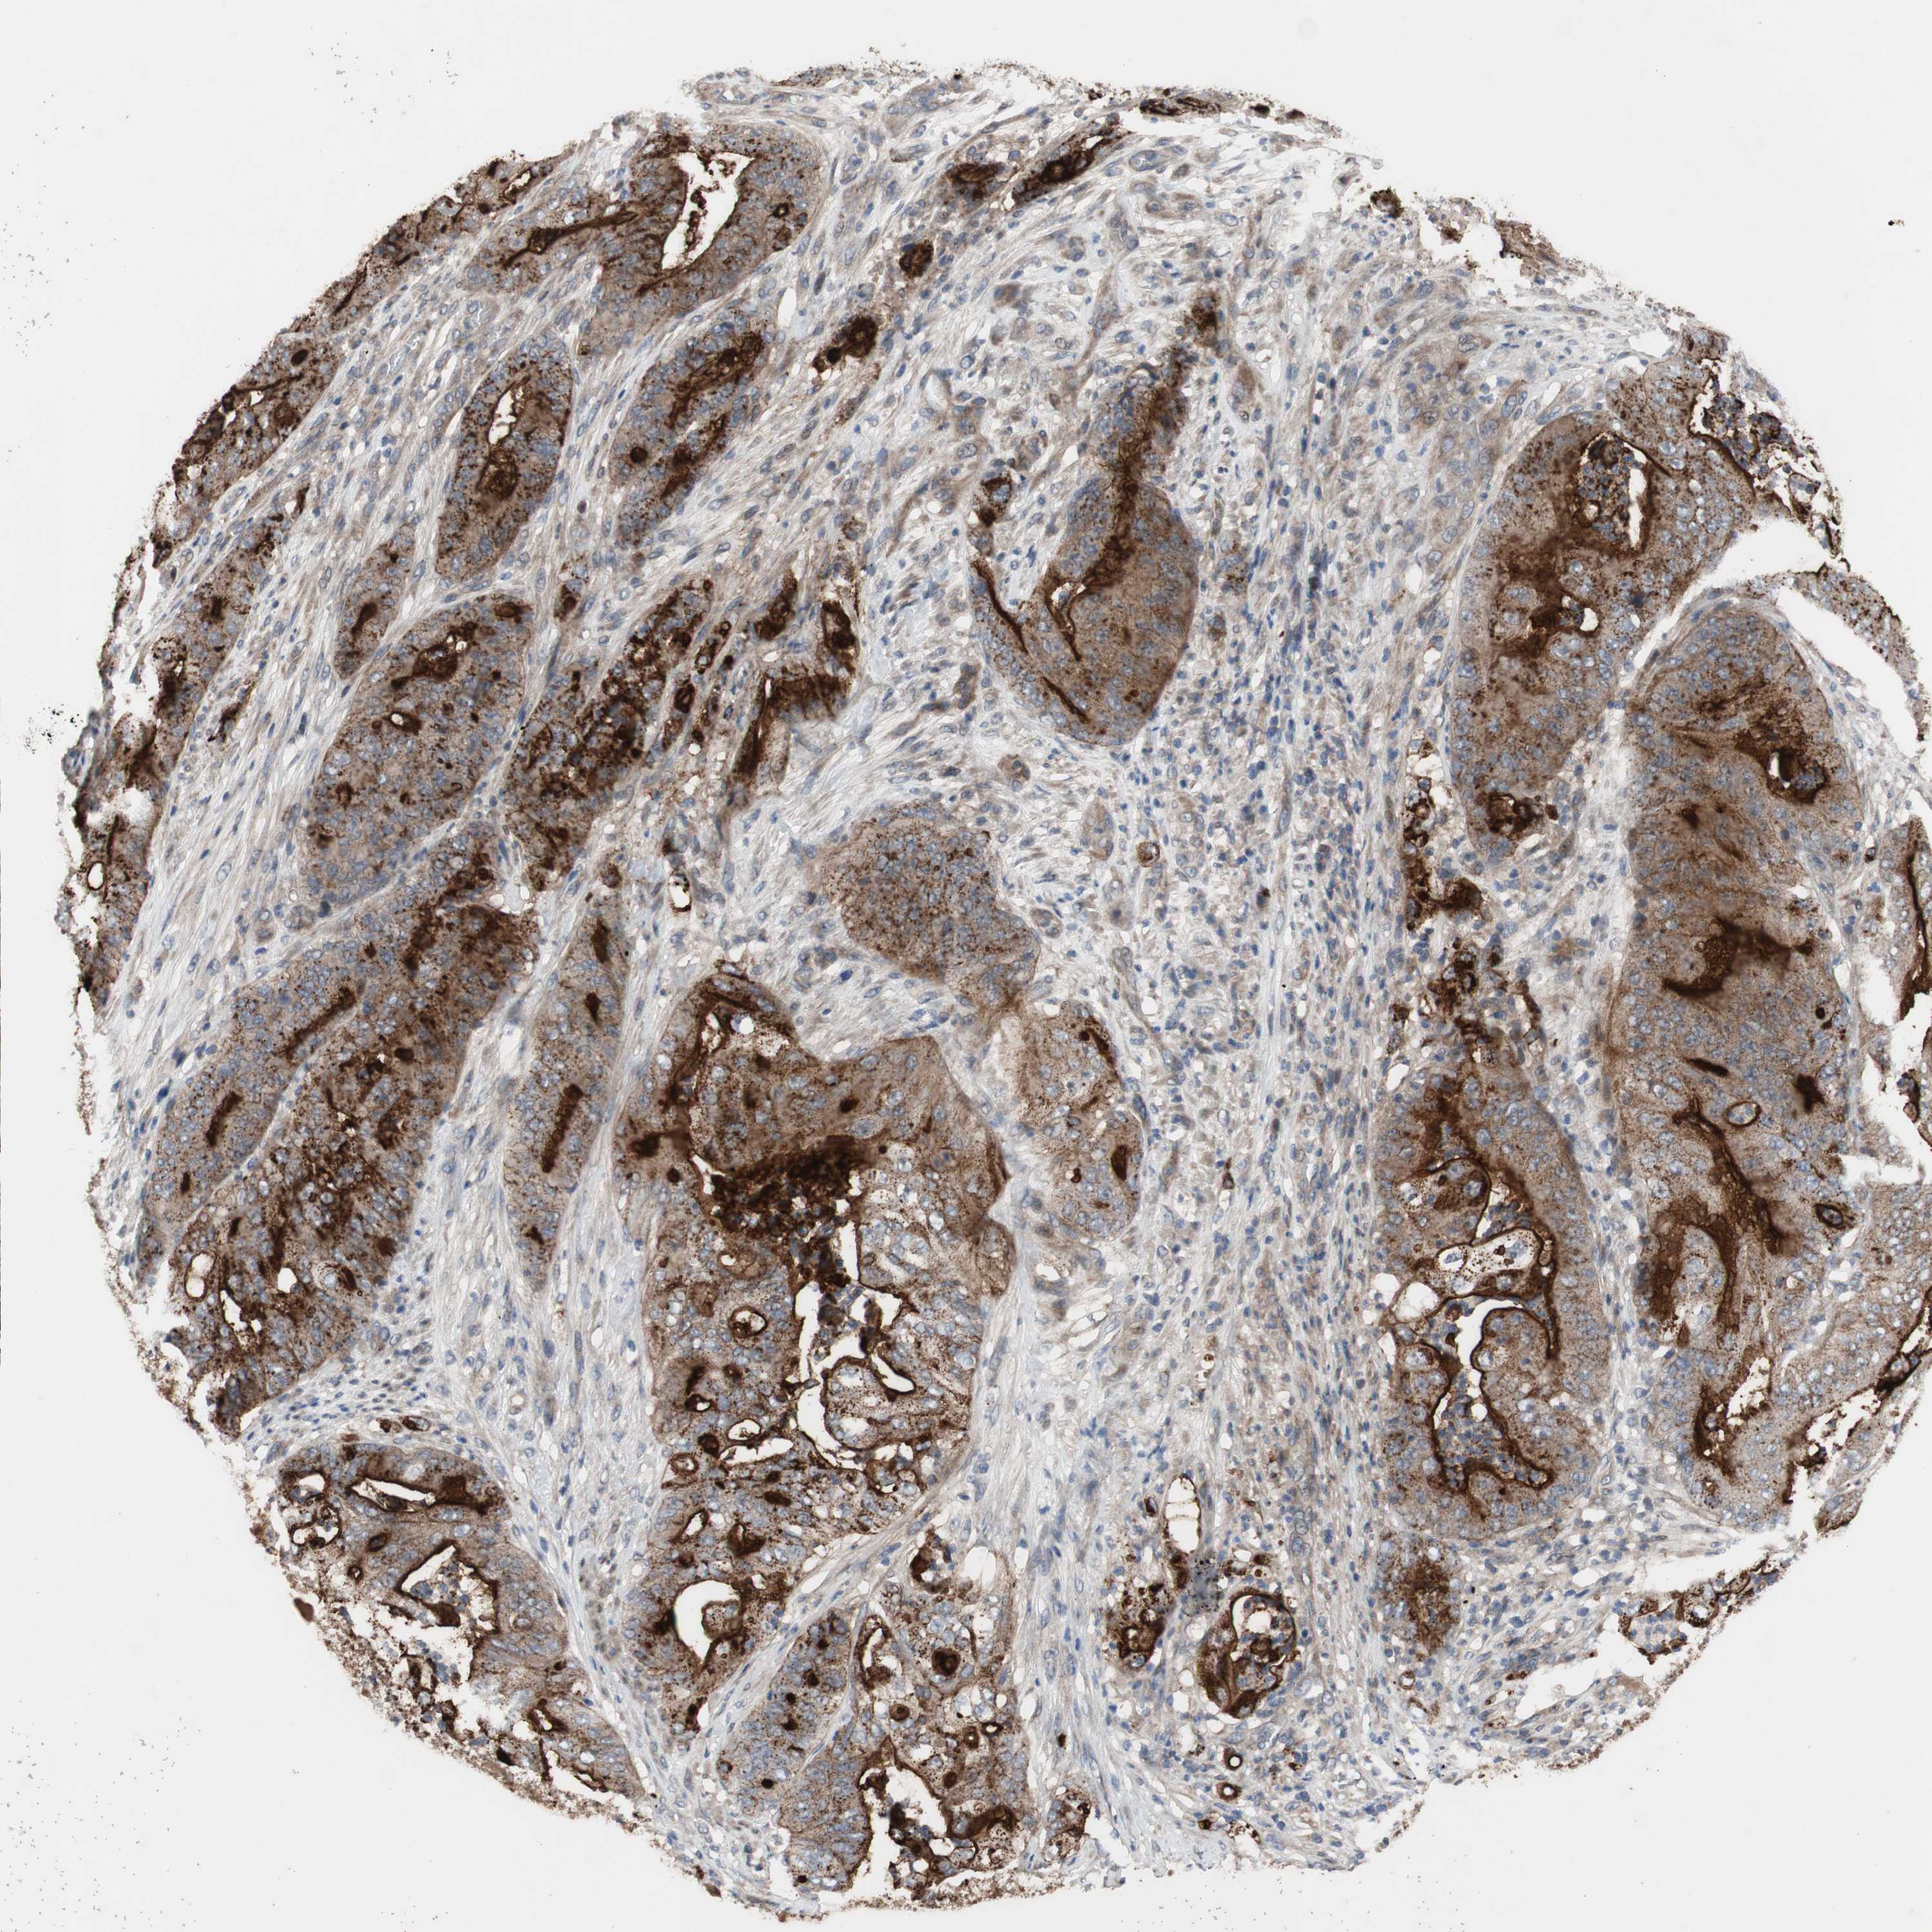

STOMACH CANCER - Protein expressioni

A mouse-over function shows sample information and annotation data. Click on an image to view it in a full screen mode. Samples can be filtered based on level of antibody staining by selecting one or several of the following categories: high, medium, low and not detected. The assay and annotation is described here.

Note that samples used for immunohistochemistry by the Human Protein Atlas do not correspond to samples in the TCGA dataset.

Antibody stainingi

Antibody staining in the annotated cell types in the current human tissue is reported as not detected, low, medium, or high, based on conventional immunohistochemistry profiling in selected tissues. This score is based on the combination of the staining intensity and fraction of stained cells.

Each image is clickable and will lead to virtual microscopy that enables deeper exploration of all samples and also displays staining intensity scores, fraction scores and subcellular localization as well as patient and tissue information for each sample.

Antibody HPA009291

Staining

High

Medium

Low

Not detected

Intensity

Strong

Moderate

Weak

Negative

Quantity

>75%

75%-25%

<25%

None

Location

Nuclear

Cytoplasmic/membranous

Cytoplasmic/membranous,nuclear

Adenocarcinoma, NOS